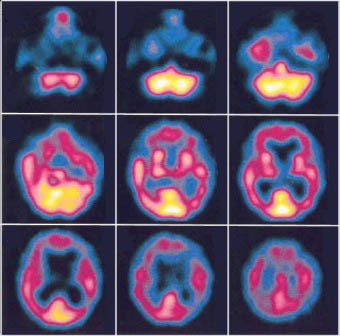

La conciencia se entiende entonces como conocimiento (por ejemplo, de «tus alegrÃas, tus penas», &c.) pero éste, desde la perspectiva reduccionista neurológica de Crick, sólo puede entenderse a su vez como un conjunto de procesos de aferencia sensorial que dan lugar a actos motores, asà como sus correspondientes patrones neurales jerárquicos donde quede «representado». Esto es lo que defiende también la psicologÃa cognitiva: el conocimiento no es una acción, directa y necesariamente ligada a sus consecuencias (para uno mismo y para otros) sino un proceso que ocurre a nivel neurológico. El conocimiento es algo diferente y previo a su manifestación, entendiendo que puede comprobarse verdaderamente su existencia con técnicas de neuroimagen; en otras palabras: mediante la observación de una pantalla digital donde diferentes zonas encefálicas cambian de color en función de lo que hace un sujeto.